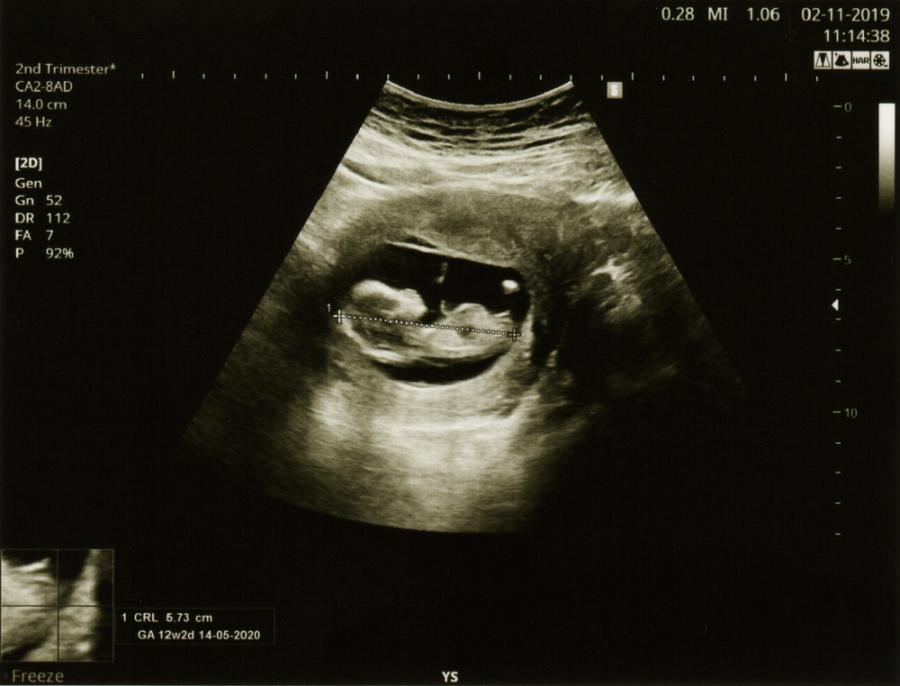

При експерименти изследователите откриха повишена активност в мозъците на новородените, чувайки езика, на който са били изложени най-често в утробата си. Проучването не е разгледало кога точно бебетата стават възприемчиви към говоримия език, докато са още в утробата, въпреки че е добре известно, че плодът започва да чува звуци в по-късните етапи на втория триместър и началото на третия. Ето защо бъдещите майки, а и бащите, не трябва да се страхуват да разговарят и дори да говорят директно на бебето си.

Вече е известно, че между петия и седмия месец от бременността плодът започва да чува звуци извън утробата. Още по-рано - на 16-ата седмица - неродените бебета могат да реагират на музика, която звучи извън утробата, като движат устата и езика си, разкри шокиращо проучване от 2015 г.